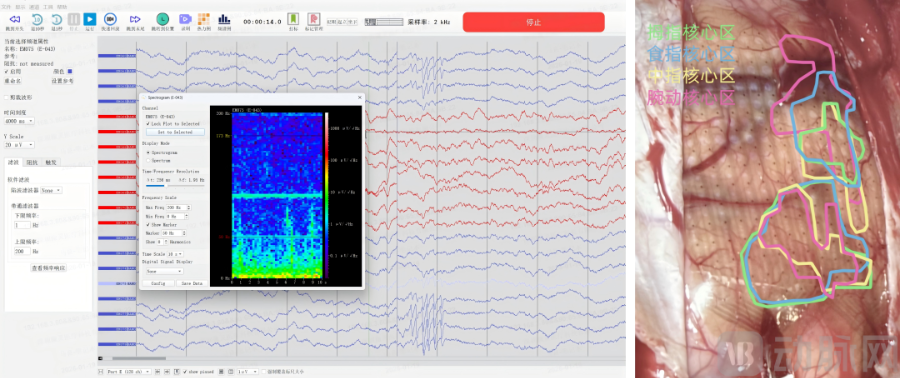

微灵医疗高通量神经电生理采集系统采集电生理信号(左)手部精细运动任务功能图谱展示(右),企业供图